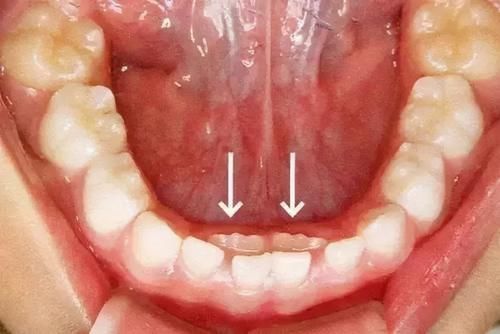

堆堆|孩子乳牙没掉,新牙就已长出?造成孩子乳牙脱落晚的原因不止一种( 二 )

比如:牙齿稀松、生长位不正、牙病、牙齿间距大等等。这些并不一定是“天生”的,可能是因为某些可变原因造成的。